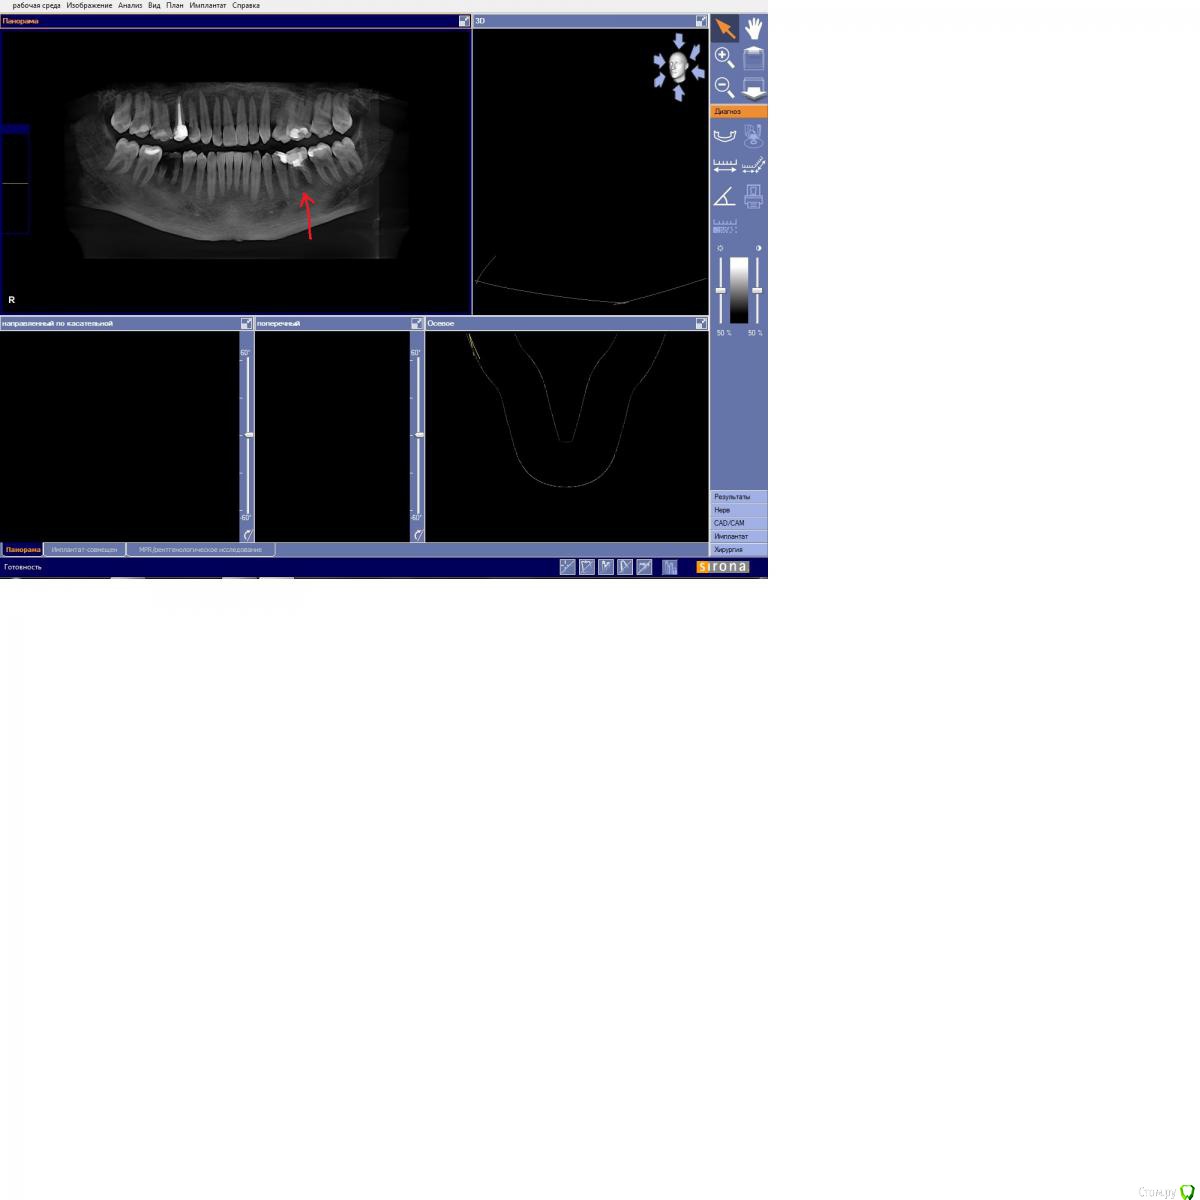

константинgh Опубликовано 17 ноября, 2016 Поделиться Опубликовано 17 ноября, 2016 (изменено) врач сказал, что надо удалять но насмотревшись роликов на youtube понял, что даже самую сложную кисту можно вылечить (можеть быть сложно, но все-таки лучше чем имплант)и еще такой момент записали на диск снимок но открывается лишь изображение в левом верхнем углу нет 3D изображения Изменено 17 ноября, 2016 пользователем константинgh Ссылка на комментарий

DmitrySH Опубликовано 17 ноября, 2016 Поделиться Опубликовано 17 ноября, 2016 Снимок мелковат. Попробуйте сделать крупнее. 1 Ссылка на комментарий